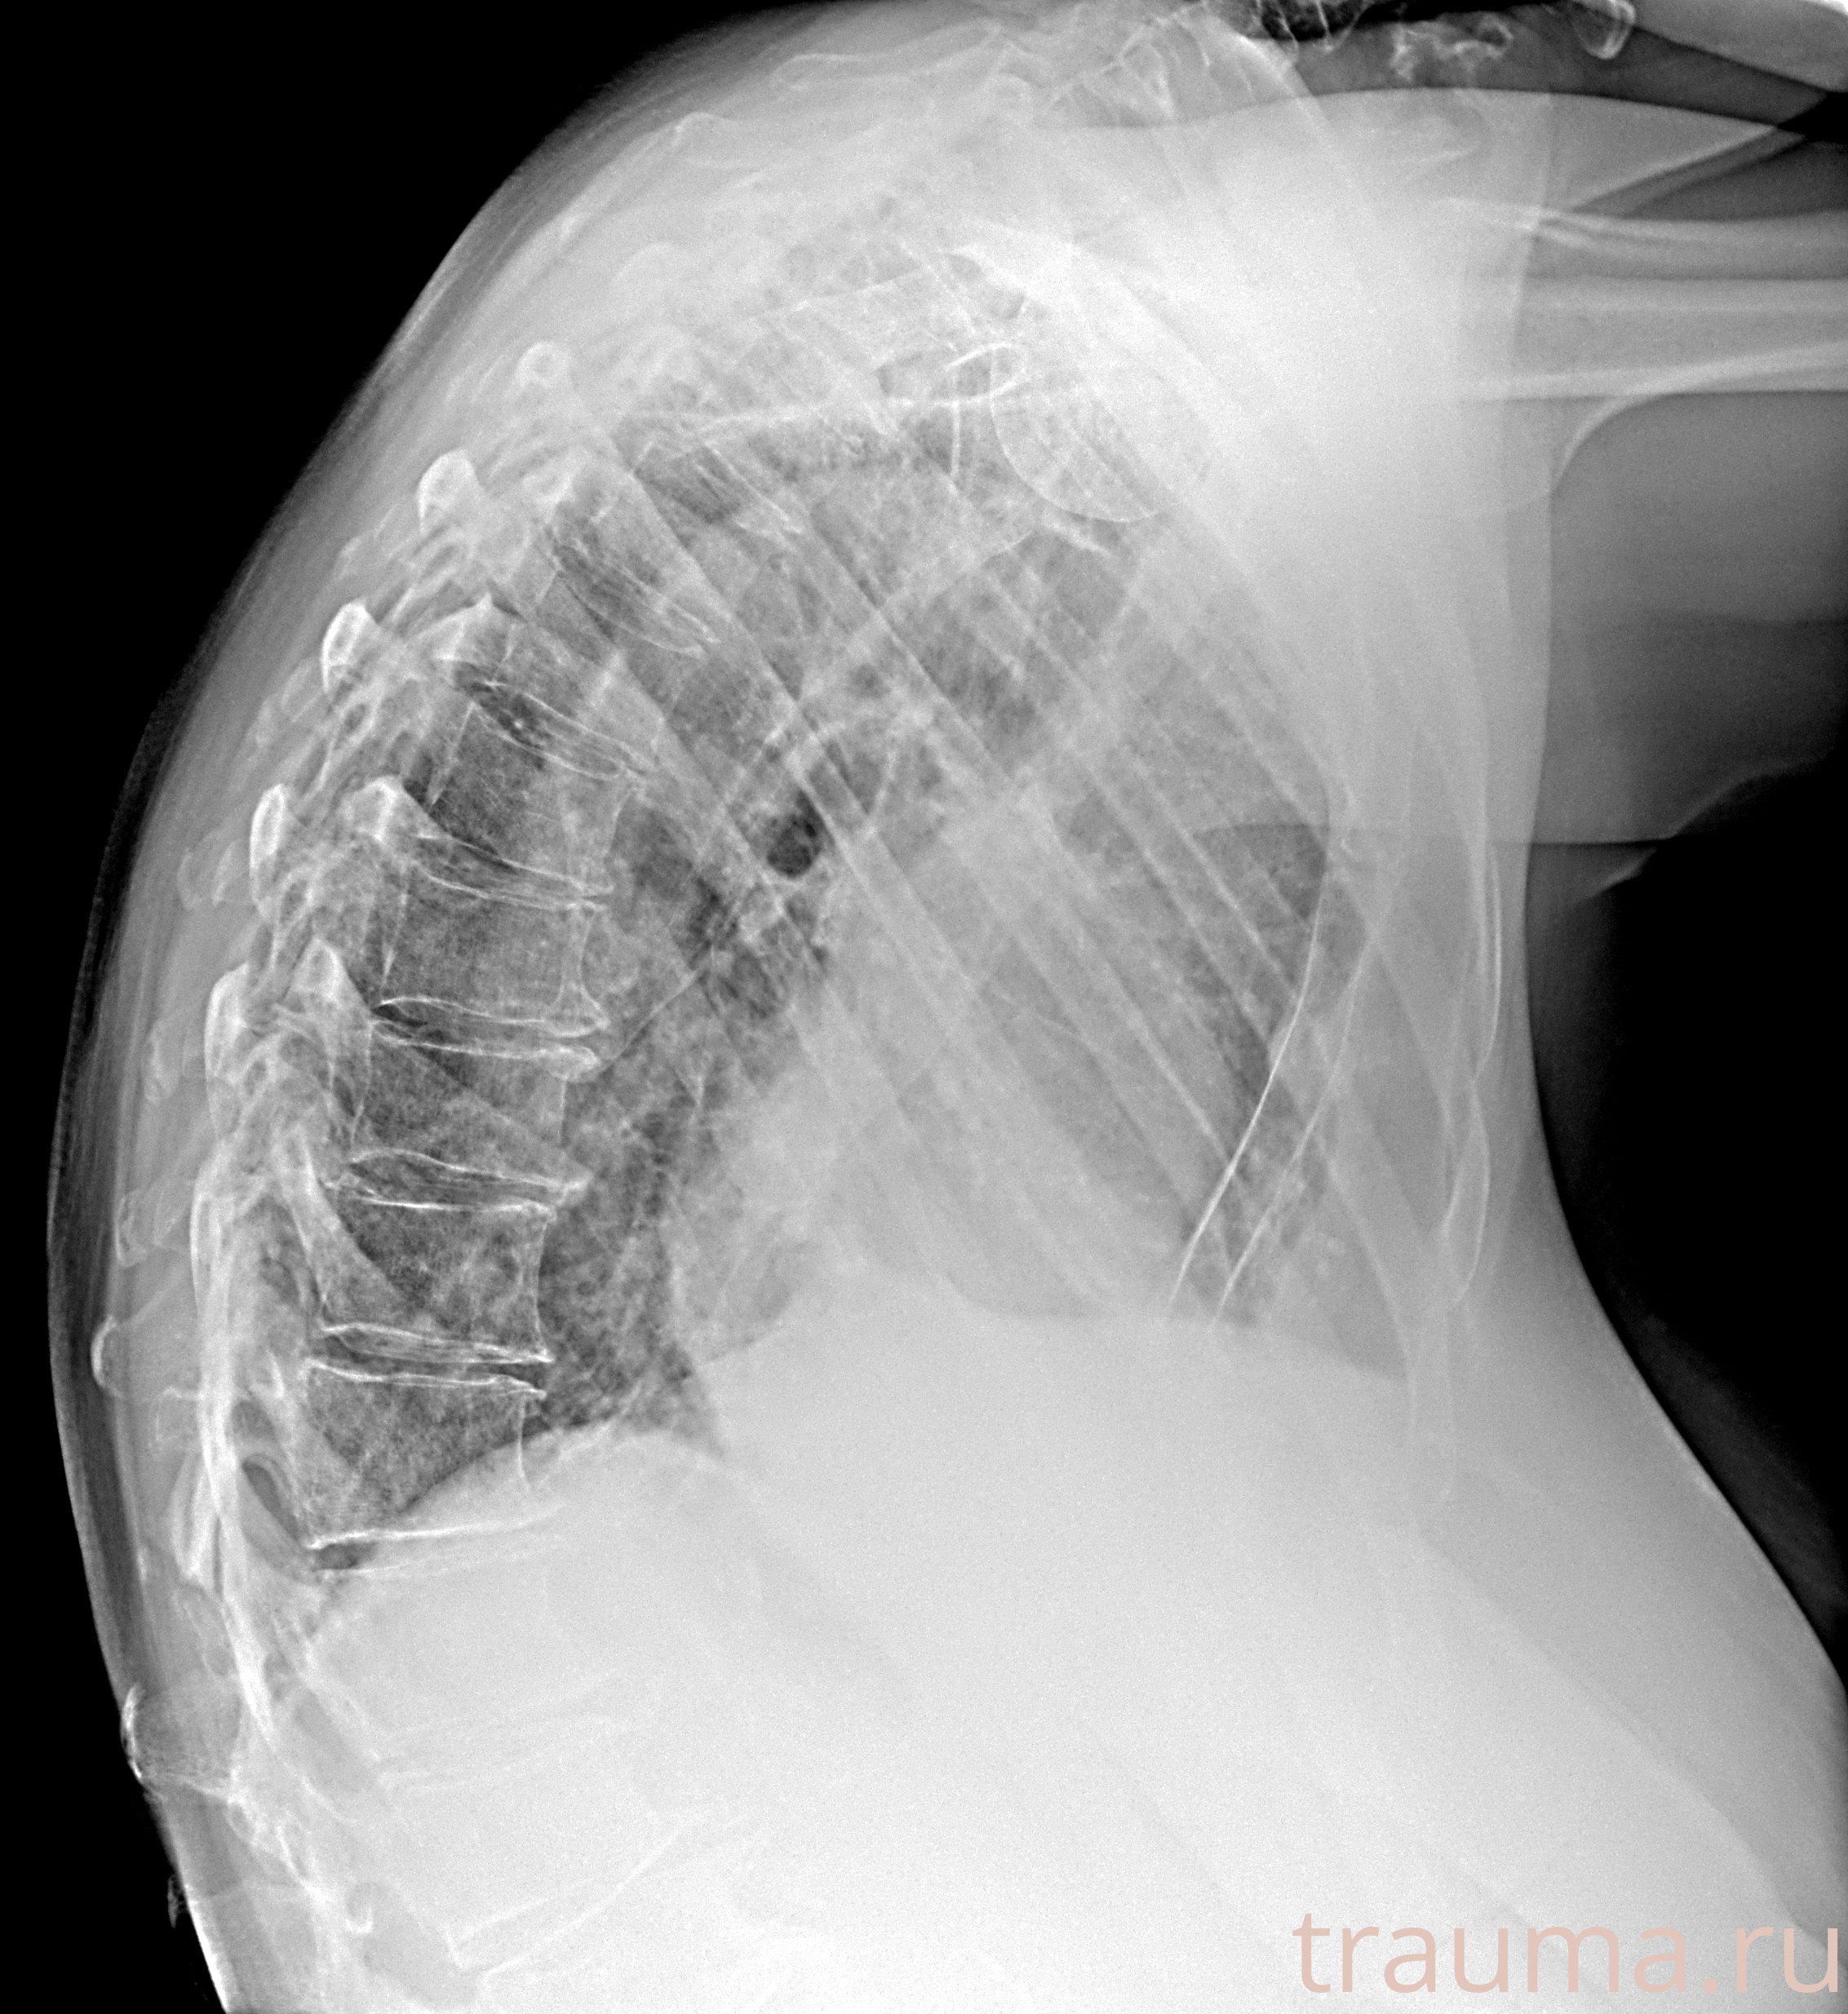

Рентгенограммы

Рентген на дому: по вашему адресу приезжает врач-рентгенолог, травматолог-ортопед с мобильным рентгеновским аппаратом, проводит диагностику травмы или заболевания, делает необходимые рентгенограммы, дает рекомендации по дальнейшему лечению. Получить качественные снимки в домашних условиях возможно благодаря уникальной методике, разработанной МосРентген Центром для института  Склифосовского

Яркость: 1   Контраст: 1   Инвертировать: 0 Увеличение: 1

Перетаскивайте мышь вверх/вниз для контраста, влево/право для яркости. Прокрутка колесом изменяет масштаб. Нажмите Сбросить для возврата к исходному изображению. При увеличении держите мышь в той области, которую хотите рассмотреть.